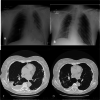

Case presentation: Two patients presented to our hospital with spontaneous pneumothorax associated with Sars-Cov2 infection onset. After initial conservative treatment with chest drain, both patients had a recurrence of pneumothorax during COVI-19 disease, contralateral (patient 1) or ipsilateral (patient 2) and therefore underwent lung surgery with thoracoscopy and bullectomy. Intraoperative findings of COVID-19 pneumonia were parenchymal atelectasis and vascular congestion. Lung tissue was very frail and prone to bleeding. Histological examination showed interstitial infiltration of lymphocytes and plasma cells, as seen in non specific interstitial pneumonia, together with myo-intimal thicknening of vessels with blood extravasation and microthrombi.